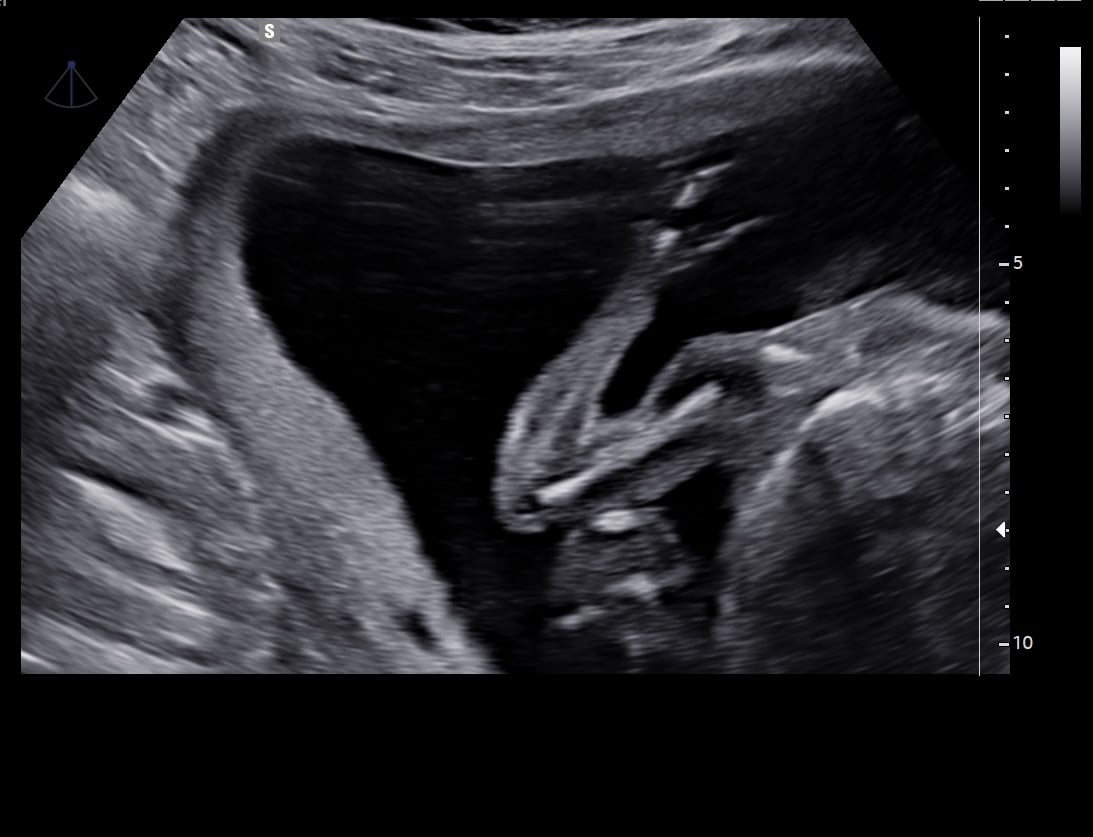

What am I looking at? Any ideas?

image.jpeg